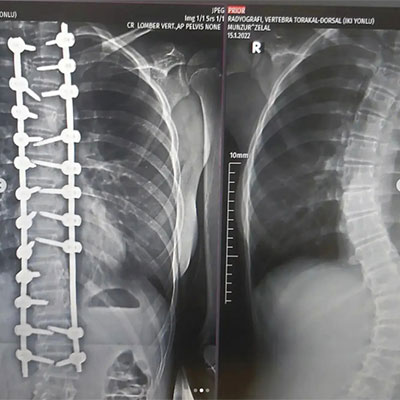

İşlem Görüntüleri

Erken başlangıç gösteren skolyozlarda ve konjenital (doğumsal ) skolyozlarda tekrar gerektiren operasyonlar yapılır. Ayrıca enfeksiyon, enstrüman (implant ) hataları, psödoartroz (kaynama sorunları )ya da tamamlanmamış cerrahi işlem durumlarında revizyon cerrahisi uygulanmalıdır.Yani; mekanik sorunlar,komplikasyonlar,enfeksiyon ve zaman içinde gelişen büyüme yada yaşlanma sorunları nediyle revizyon gerektiren skolyoz ve kifoz hastalarına kliniğimizde tecrübeli ekip dahilinde cerrahi müdahaleler gerçekleştirilmektedir .